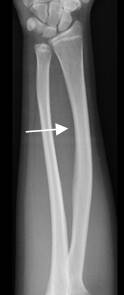

Fig 177. Fractura de Bowing.

Rx AP. Presencia de curvatura lateral en la diáfisis del radio, por deformidad plástica.